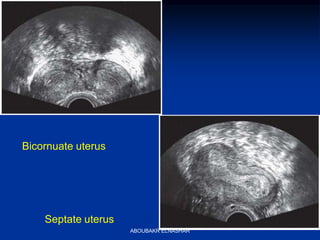

Bicornuate uterus

Septate uterus

Bicornuate

•Fundus indented

•Variable degree of

separation of uterine

horns that can be

complete, partial or

minimal

•Minimal reproductive

problems, however can

have pregnancy loss, PTL

•HSG won’t dx, need

laparoscopy

Septate

•Normal external surface,

•need laparoscopy to dx

•Septum can cause

infertility,

recurrent midtrimester

loss

Septate or bicornuate?